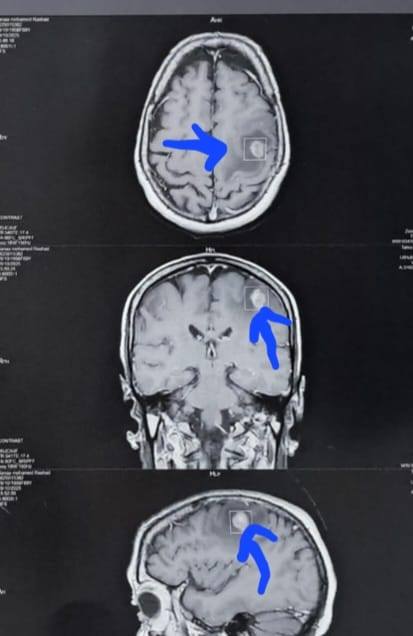

وكشف الدكتور إبراهيم الغريب رئيس قسم جراحة المخ والأعصاب بالمستشفى، أنه تعود تفاصيل الحالة إلى استقبال المستشفى المريضة بالعيادة الخارجية وهي تشكو من تنميل وضعف بالجانب الأيمن وثقل بسيط في الكلام، وبإجراء الفحوصات اللازمة من أشعة مقطعية ورنين مغناطيسي بالصبغة، تبين وجود ورم بالمخ، وتم إعطاؤها العلاج المناسب لحين استكمال الفحوصات.

وأشار، إلى أنه تم أخذ عينة من الورم لتحديد طبيعته ووضع الخطة العلاجية المناسبة، وخرجت المريضة من غرفة العمليات في حالة مستقرة.

أشعة المريضة

الأشعة الخاصة بالمريضة

الأشعة